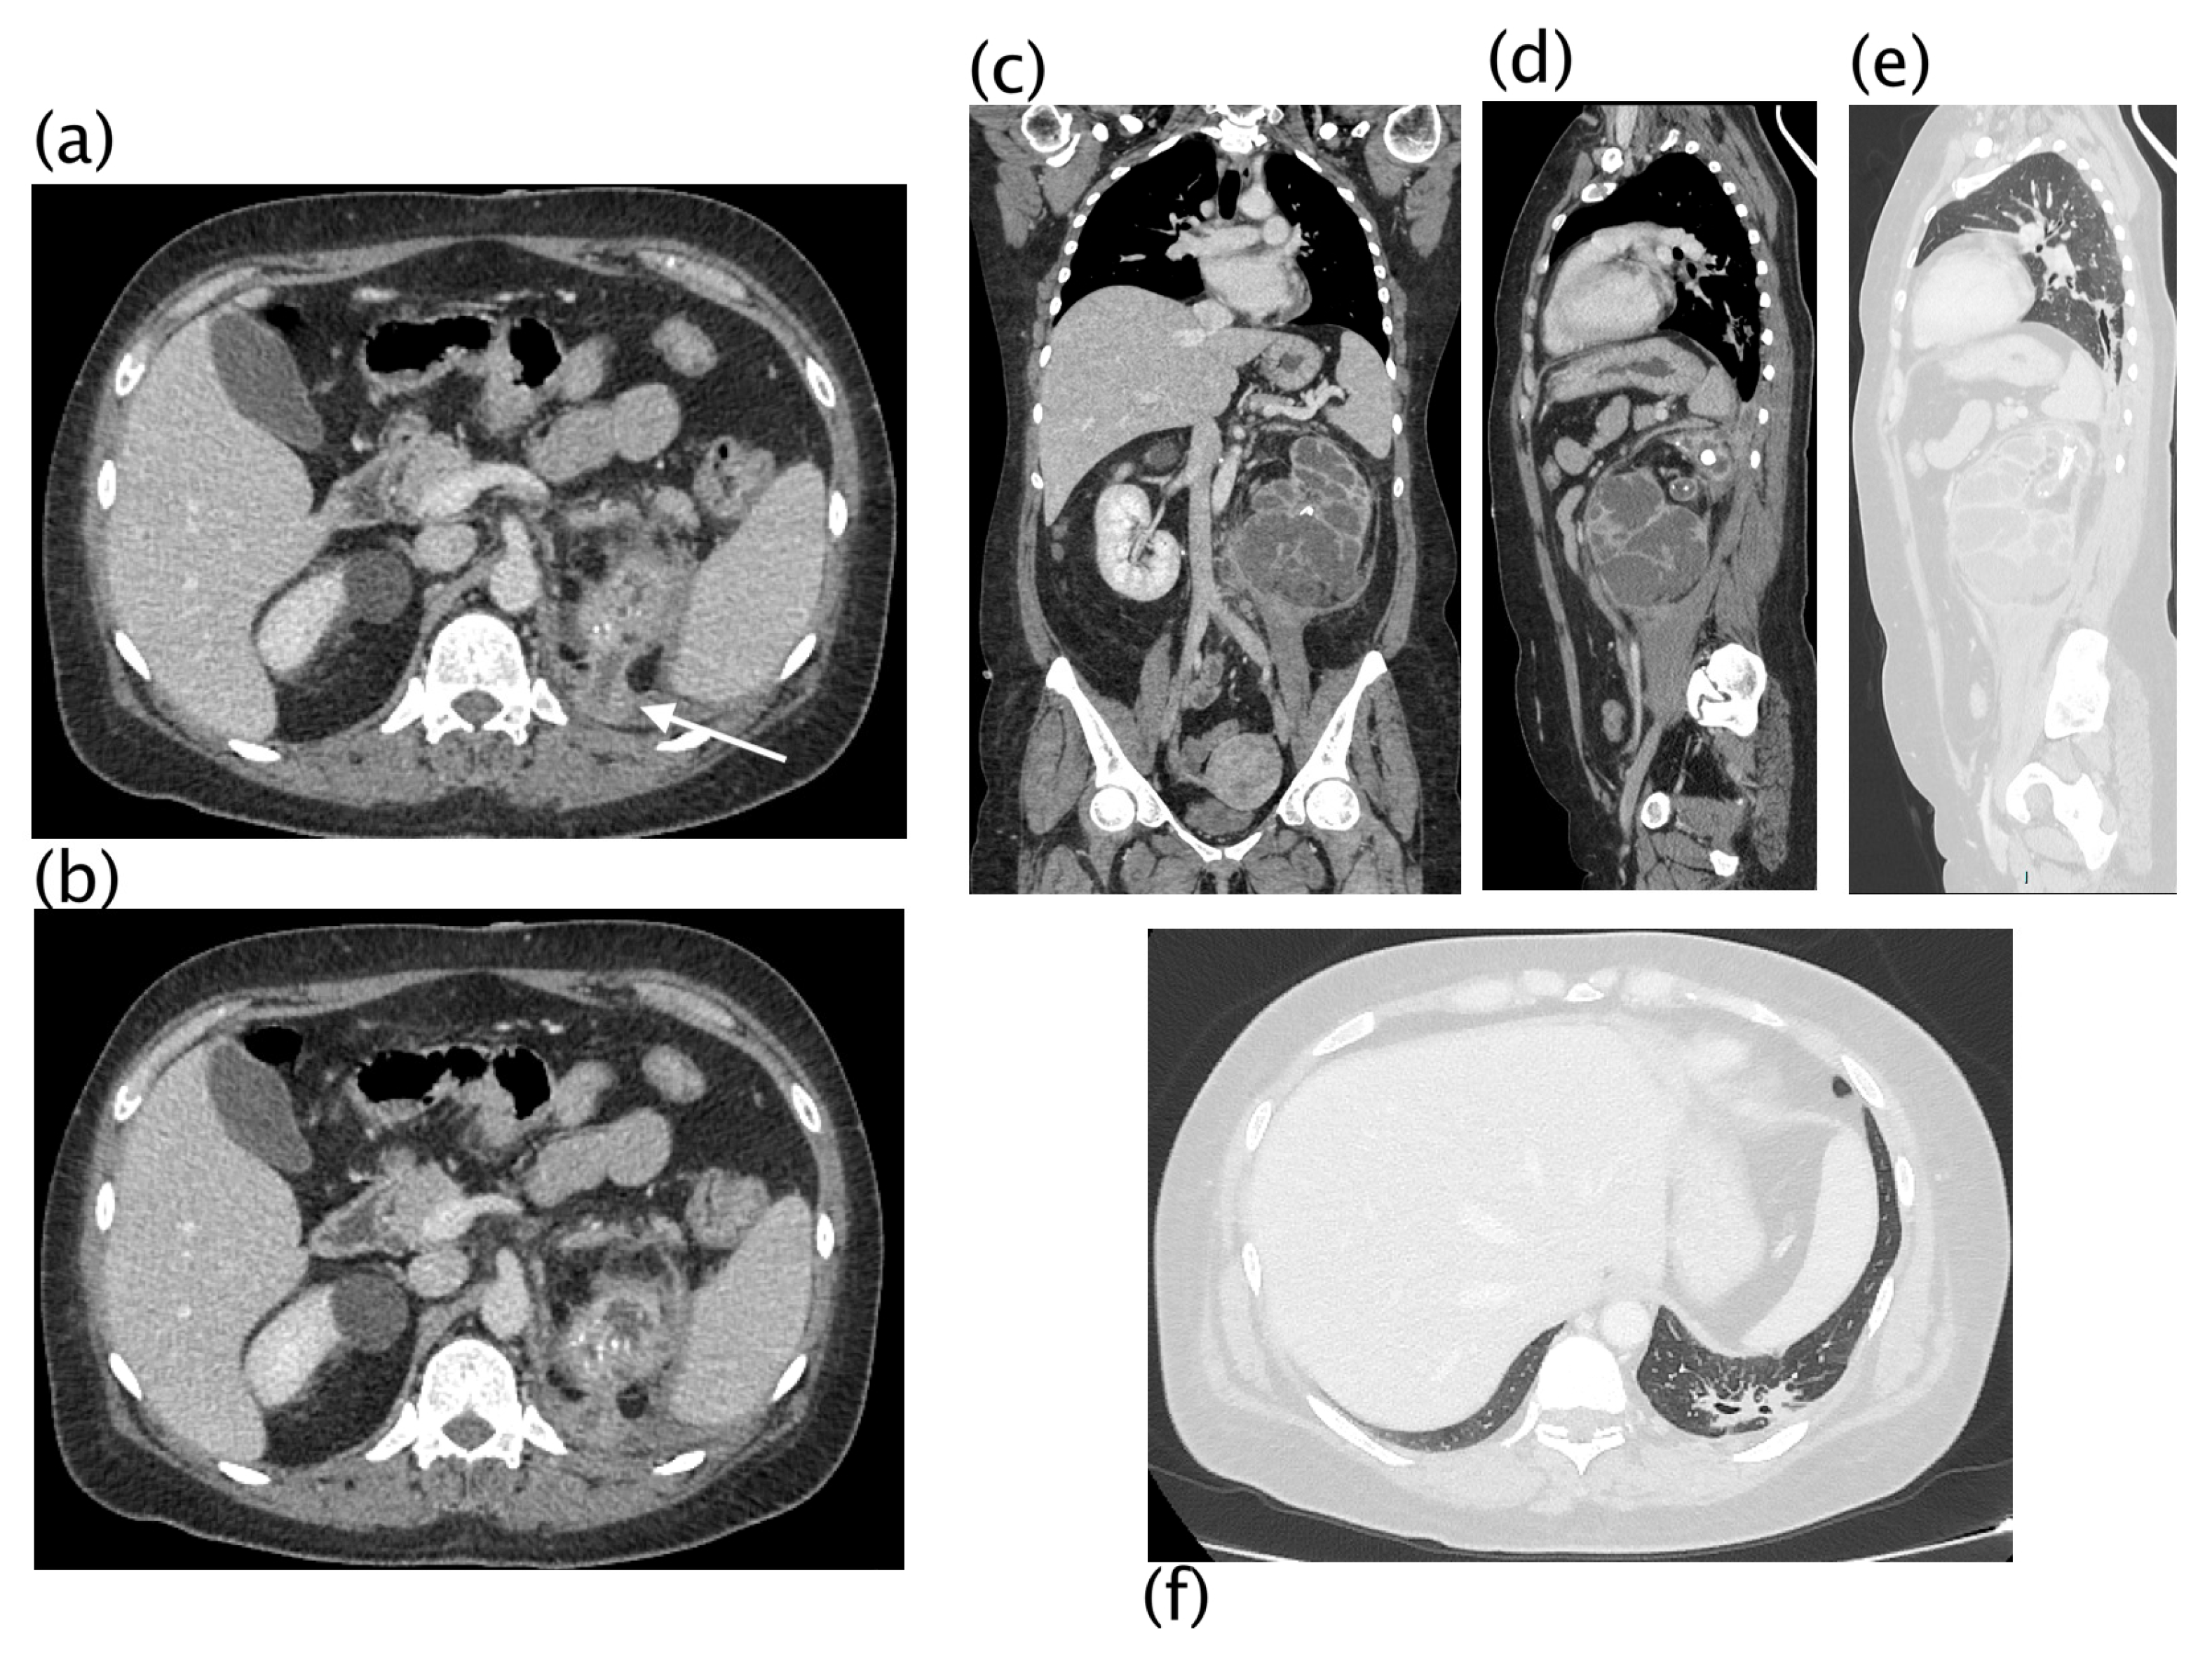

Xanthogranulomatous pyelonephritis Stage I—nephritic form. CT with contrast agent: axial (a,b) and coronal MPR reconstruction (c). The left kidney is increased in volume with a characteristic “contracted” appearance of the renal pelvis. The renal parenchyma is extremely thinned and characterized by the presence of multiple hypodense areas representing both intraparenchymal collections of pus and dilated calyces. The wall of the pyelocaliceal structures is thickened and hyperemic due to granulation tissue and parenchymal compression caused by abscess cavities. Staghorn lithiasis is present. Perirenal fat is thickened but no peri- or pararenal collections are present. No fistulas or abscesses are evident. The characteristic “bear paw sign” and contracted appearance of the pelvis allowed for the diagnosis of XGP, confirmed on histologic examination. The “bear paw sign” was appreciated on the CT scan in 66.67% of patients.